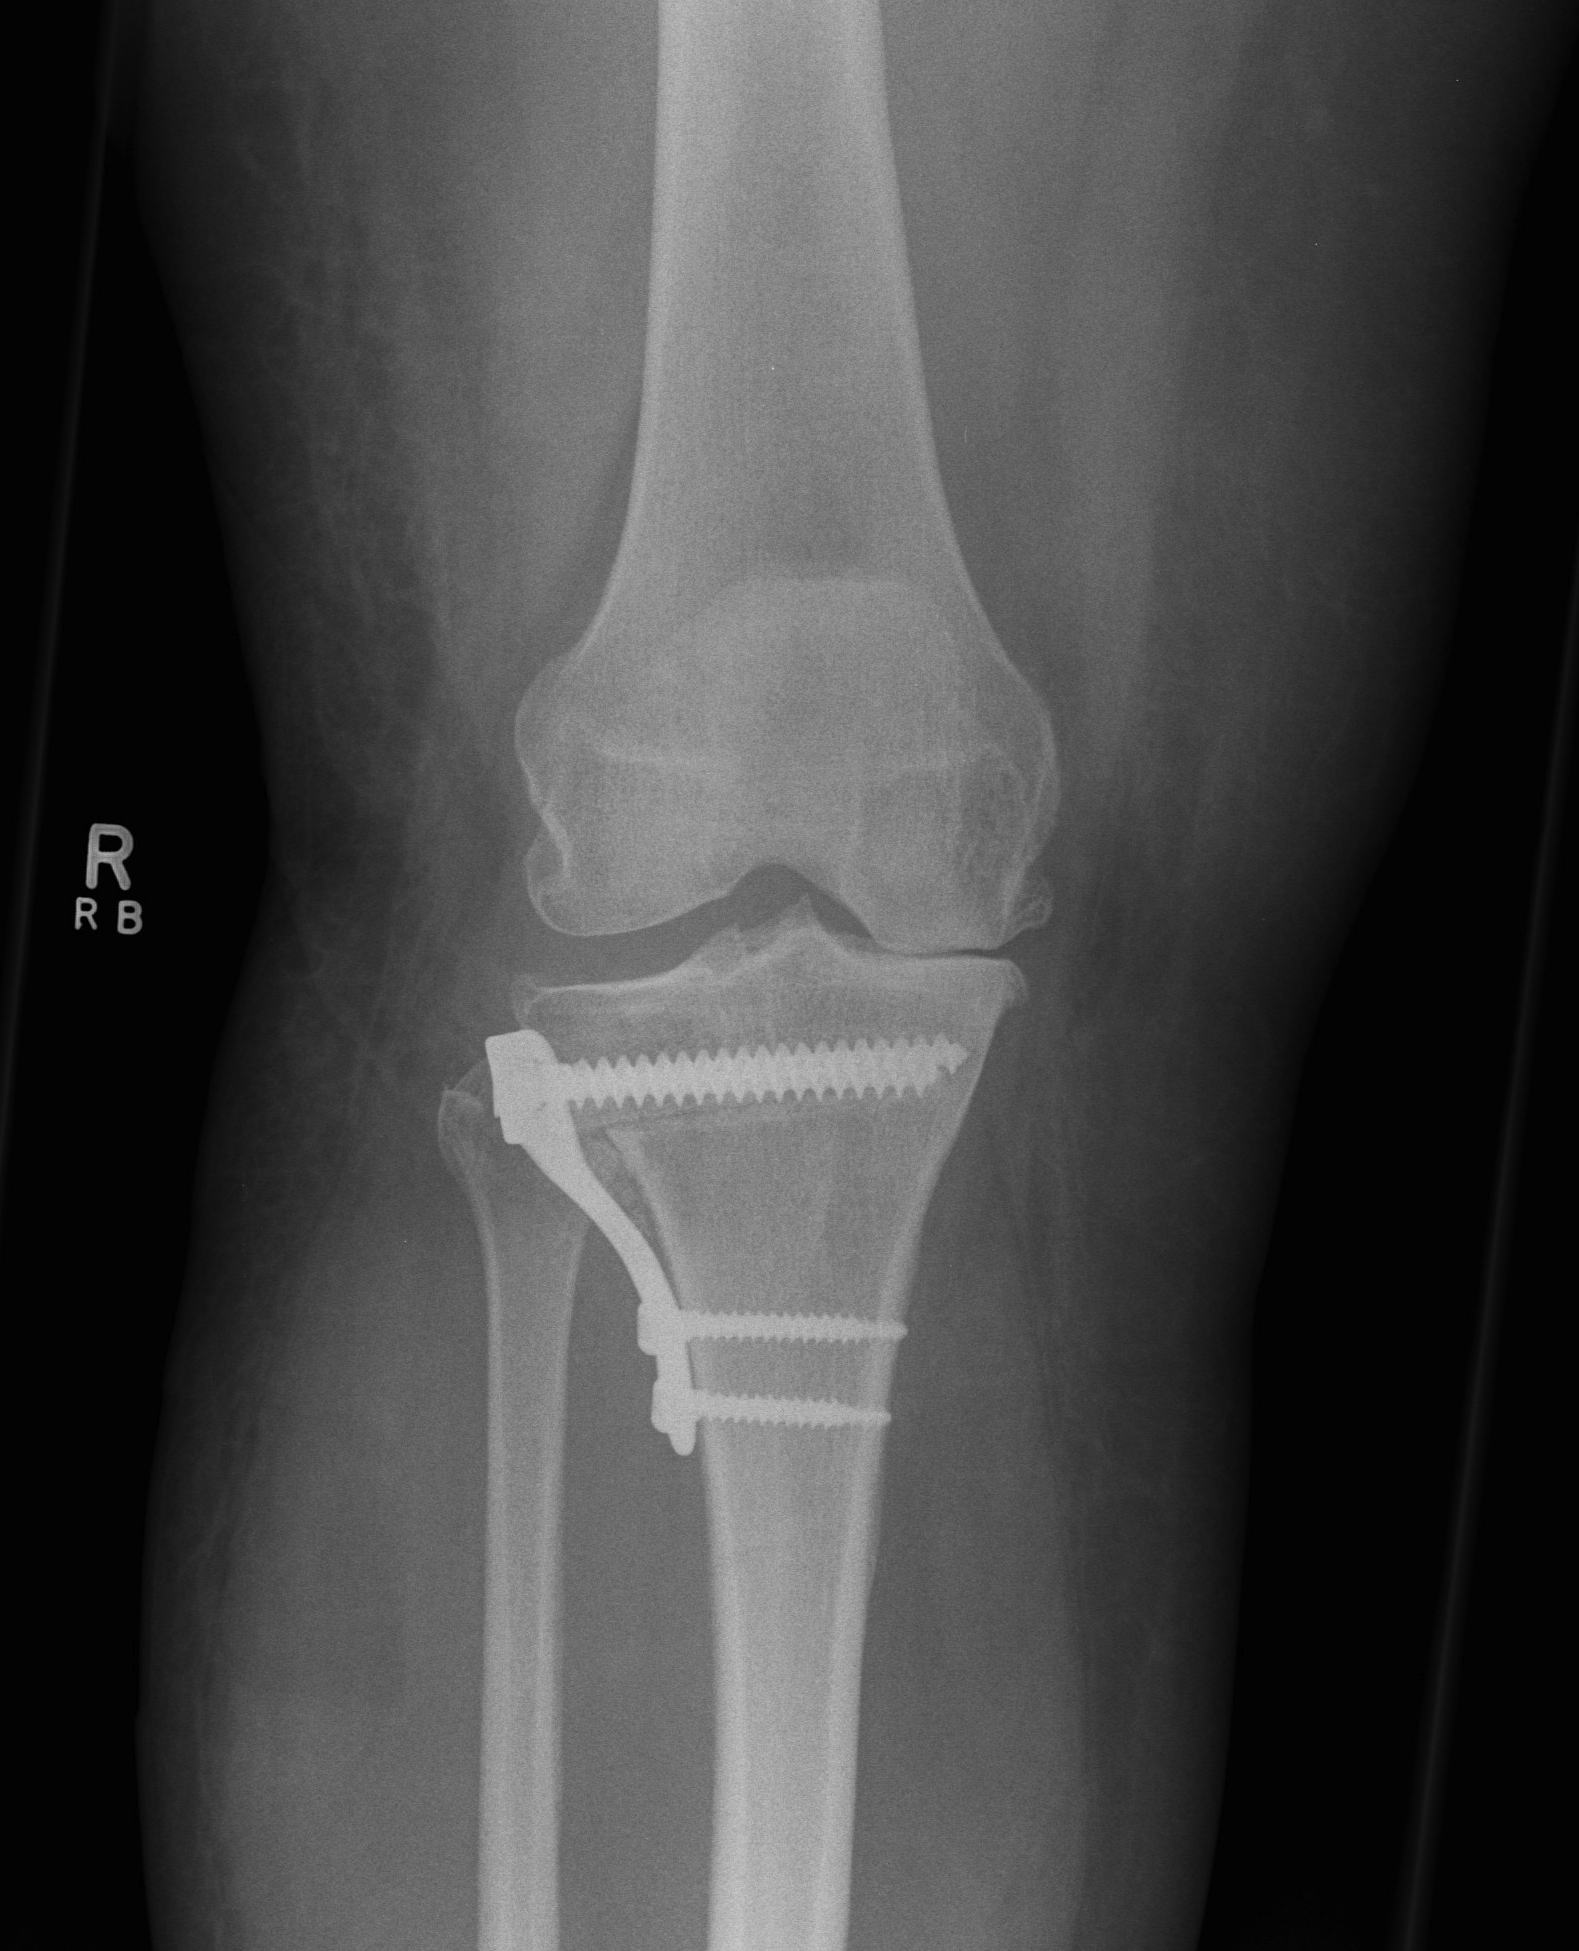

Preoperative Calculations

Calculate Desired Correction on Long Leg Views

1. Simple Calculations

Measure anatomic femoral tibial angle

- normally 5-8o

Calculate correction desired

- need to overcorrect to 8o femoro-tibial alignment

- or correct to mechanical axis of 180o